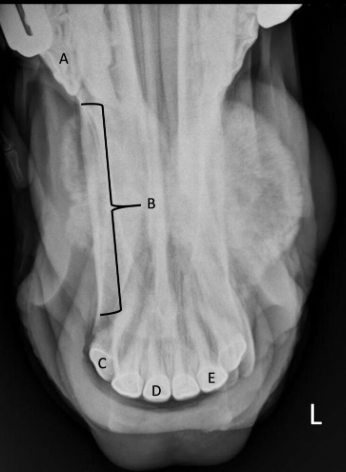

Identify the labeled anatomic structures

A

A = first premolar

B = interalveolar space

C = 403

D = 401

E = 302